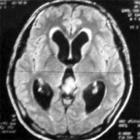

5.腦CT檢查:可顯示腫瘤所在的部位、側腦室大小及形狀,對腦室內腫瘤的診斷提供依據。

6.MRI檢查:可顯示腫瘤所在的部位、大小及形狀,來源於腦室內或腦室外、與周圍腦組織關係等,提供可靠的依據。